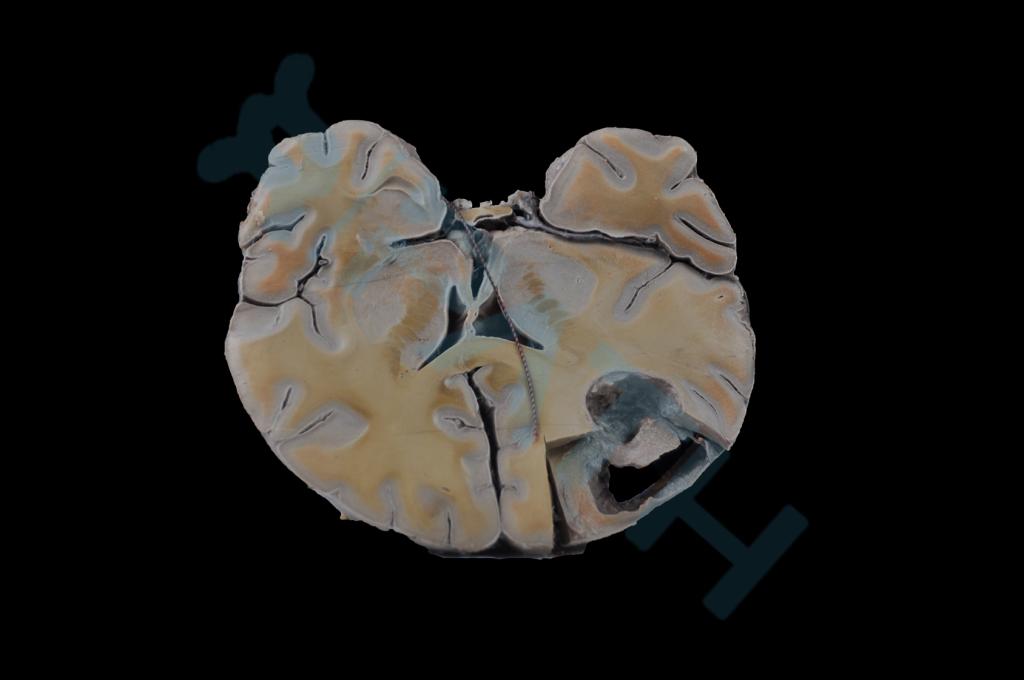

神经系统疾病

脑脓肿(1)